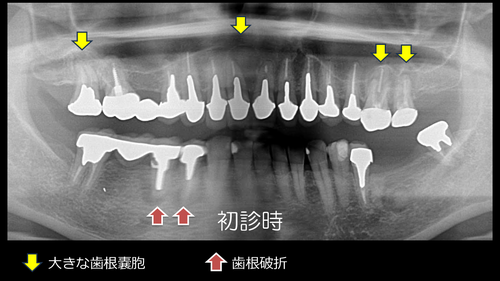

初診時の写真は↑です。54歳女性。

お若い頃から歯では悩まされていたとのことです。全体的な治療をご希望され、90分かけて奈良県から来院されました。

クラウンなどのやり替えも行っていますが、今回はオペだけに焦点を当て、治療内容を説明します。

上下左右にインプラントを埋入しました。抜歯即時インプラント埋入や即時荷重(その日のうちに仮歯を入れて噛めるようにする治療)を駆使しています。

スライド5.PNG前歯部の大きな歯根嚢胞の摘出も非常に経過良好です。